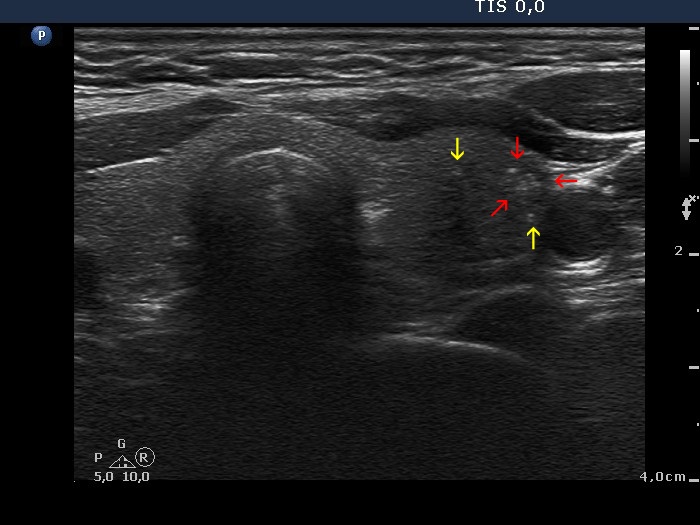

Papillary carcinoma (histology) - case conp016

Transverse scan

Longitudinal scan

The less hypoechogenic area pointed with red arrows located lateral to the main body of the tumor is suspicious being presentation of infiltration of the parenchyma. The right, longitudinal scan is more obvious: the area pointed with yellow arrows upper to the main body is caused very likely by spread of the tumor into the normal parenchyma.